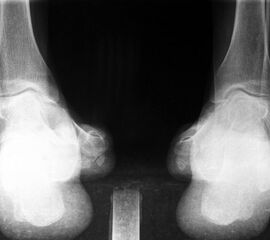

• Fuß belastet dp und seitlich (Abb. 14 und 15)

• Saltzman view (Abb. 16)

Zum Lesen der Bildbeschreibung und zur Vollansicht bitte die Bilder anklicken. Bilder: A. Simon

Typische Merkmale des Saltzman View

• Calcaneus steht varisch zur Tibialängsachse

• Der erste Zehenstrahl ist medial erkennbar

• Konsekutive varische Gelenklinie des oberen Sprunggelenkes